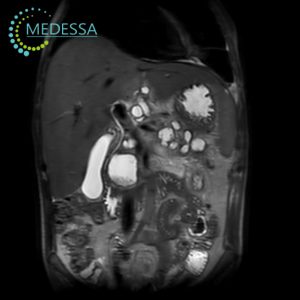

MRI of the Abdomen and Biliary Tract

- Unexplained abdominal pain or discomfort.

- Unintentional weight loss or appetite changes.

- Abnormal liver or gallbladder laboratory results.

- Suspected tumors, cysts, or other masses.

- Gallstone disease.

- Inflammatory conditions (cholecystitis, cholangitis).

- Preoperative assessment.

MRI with Contrast Enhancement

Contrast agents may be used for improved visualization of tumors, inflammatory changes, and vascular abnormalities. The decision to administer contrast is made individually by the physician.